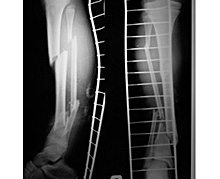

Операция обычно осуществляется с использованием интрамедуллярных конструкций. Предпочтительна фиксация штифтами или остеосинтез диафизарных переломов большеберцовой кости блокирующими стержнями. Накостные фиксаторы (пластины, болты и винты) используются реже, поскольку могут вызвать разрастание надкостницы. Однако иногда их выбор оправдан характером перелома - например, при длинной спиральной линии излома, когда отломки плохо удерживаются внутрикостными конструкциями. Аппараты Илизарова у детей используются редко.